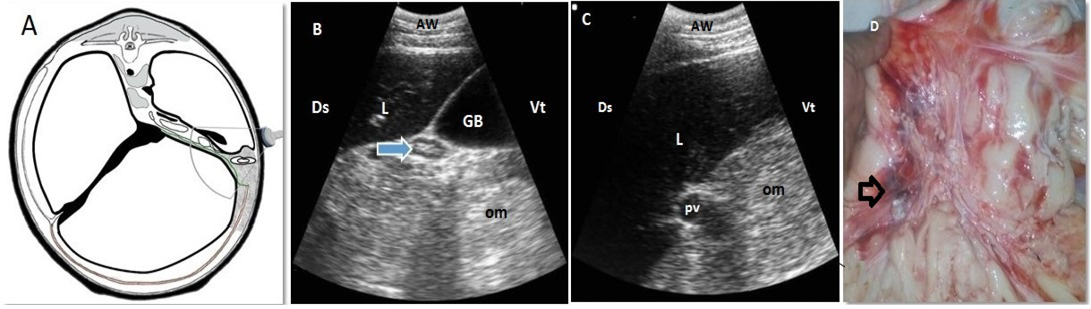

Omental fat necrosis “lipomatosis” of 3-years and 6-months-old-cow. A. Cross-section schematic drawing of abdomen at the level of 13th thoracic vertebra. Note the location of the disease and the transducer. B, C. Ultrasonogram of ventral part of right 10th intercostal space. Note presence of echogenic masses within the omentum (om) with invisible intestinal loops and a compressed duodenum (arrow). D. Lesions presented at necropsy. Note the reddish and blackish discoloured omentum fatty tissues (arrow). AW: abdominal wall; L:liver; GB: Gallbladder; pv: portal vein, Ds: dorsal; Vt: ventral